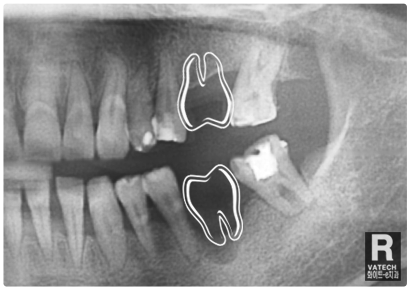

:: 엑스레이 촬영을 통하여 살펴보는 뼈이식 & 임플란트 ::

공간 확보를 위한 엑스레이 촬영

이렇게 임플란트 인공치아 뿌리를 식립하려 하는 자리에

엑스레이 촬영을 통해 공간을 먼저 봅니다.

임플란트 의사 결정

원래라면 저런 어금니 두개가 들어가 있던 자리였죠.

하지만 없으니 임플란트 궈궈!

잇몸뼈 소실 복구

자~ 눈금으로 쉽게 표기해 드릴게요.

보시다시피 옆자리의 잇몸뼈의 높이보다 상당히 내려가

있습니다. 치아가 자리에 없는 동안 많은 잇몸뼈 소실이

원인입니다.

인공치아 뿌리 식립

이렇게 잇몸뼈 이식술을 통해 인공치아 기둥뿌리를 확실히

심어주는 것입니다!